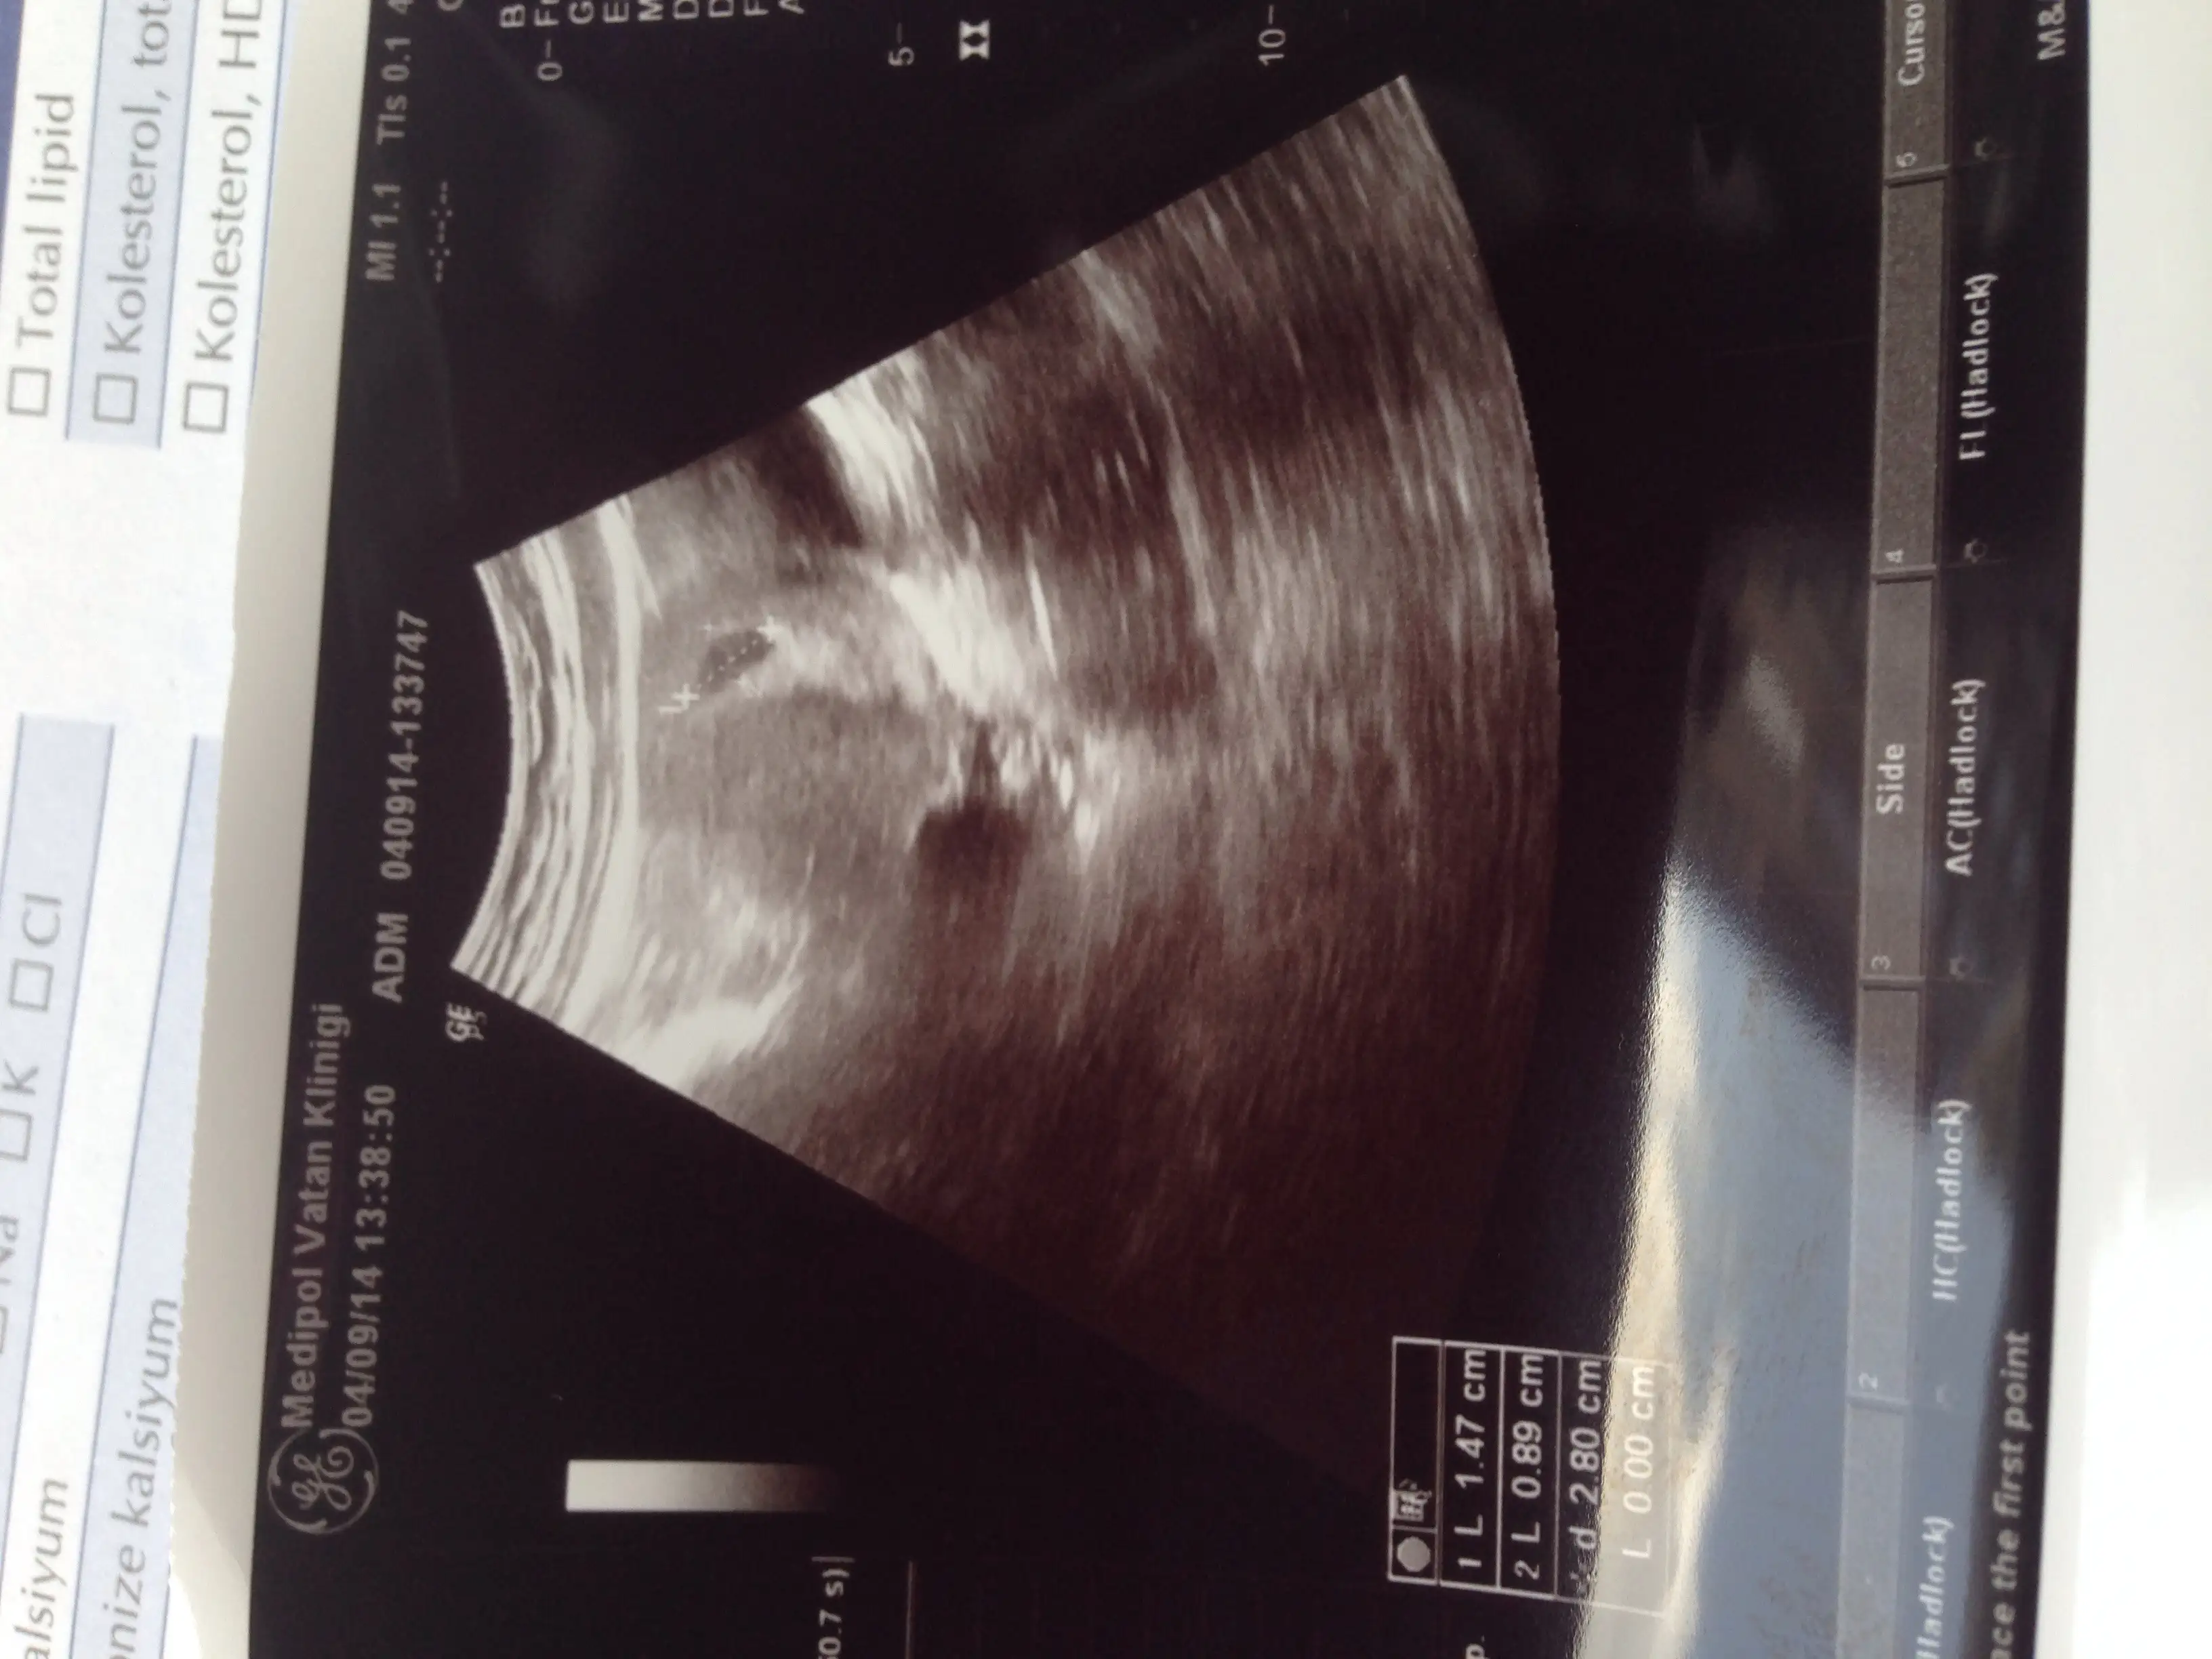

dün ise maşallah hem kesemizi hemde bebişimizi gördük.

ve benim ultrason görüntüm kızlar....